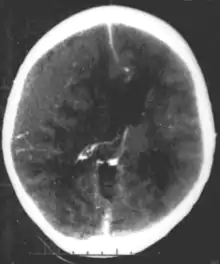

| Epidural hematoma as seen on a CT scan with overlying skull fracture. Note the biconvex shaped collection of blood. There is also bruising with bleeding on the opposite side of the brain. | |

Epidural hematomas usually appear convex in shape because their expansion stops at the skull's sutures, where the dura mater is tightly attached to the skull. Thus, they expand inward toward the brain rather than along the inside of the skull, as occurs in subdural hematomas. Most people also have a skull fracture.[3]